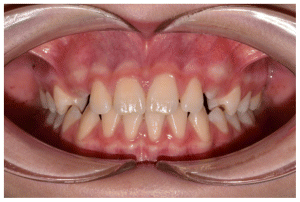

Case 2

The patient was a growing female child who presented during early mixed dentition with an anterior crossbite associated with a deep overbite and a marked sagittal discrepancy (Figures 12–19). The initial clinical examination revealed a negative overjet, complete anterior deep bite, and a functional Class III occlusal pattern. Extraoral assessment showed a flattened facial profile, while cephalometric analysis confirmed a skeletal imbalance characterized by increased SNA and SNB values, an ANB of 0°, negative Withs appraisal, and significant dentoalveolar compensations, including proclination of both upper and lower incisors (Table 3). The vertical pattern was predominantly hypodivergent, suggesting a high risk of unfavorable mandibular growth progression if left untreated. Given the patient’s young age and growth potential, an early interceptive treatment was planned to use the AMCOP® TC appliance, with the aim of correcting the anterior crossbite, improving neuromuscular balance, and guiding sagittal and vertical development during growth. The appliance was worn nightly and for additional daytime hours, according to patient compliance.

After 18 months of treatment, a clear clinical improvement was observed. Intraoral examination demonstrated complete correction of the anterior crossbite, with establishment of a positive overjet and normalization of the anterior occlusal relationship. The deep bite was reduced, allowing more functional anterior guidance. Occlusal relationships improved toward a stable dental Class I, and the need for excessive dentoalveolar compensation was reduced. Cephalometric reassessment showed an overall improvement in sagittal relationships and incisor inclinations, with a trend toward normalization of the previously altered parameters. These findings indicate that early functional therapy with the AMCOP® TC appliance was effective in intercepting the developing Class III malocclusion, improving occlusal function, and potentially reducing the severity of future skeletal discrepancies (Table 4).